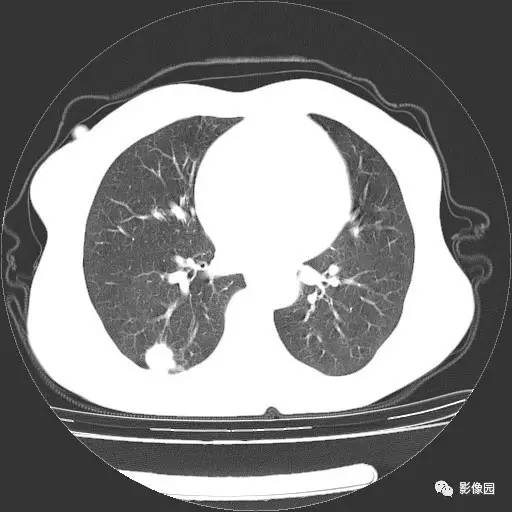

右肺下叶鳞癌1例CT

女,52岁,体检胸片发现右肺下叶小结节,患者无咳嗽、咳痰及咯血等症状。患者不同意增强检查。 医学百科网 | YxBaike.Com

手术后病理结果:(右肺下叶)鳞癌。 医学百科网 | YxBaike.Com